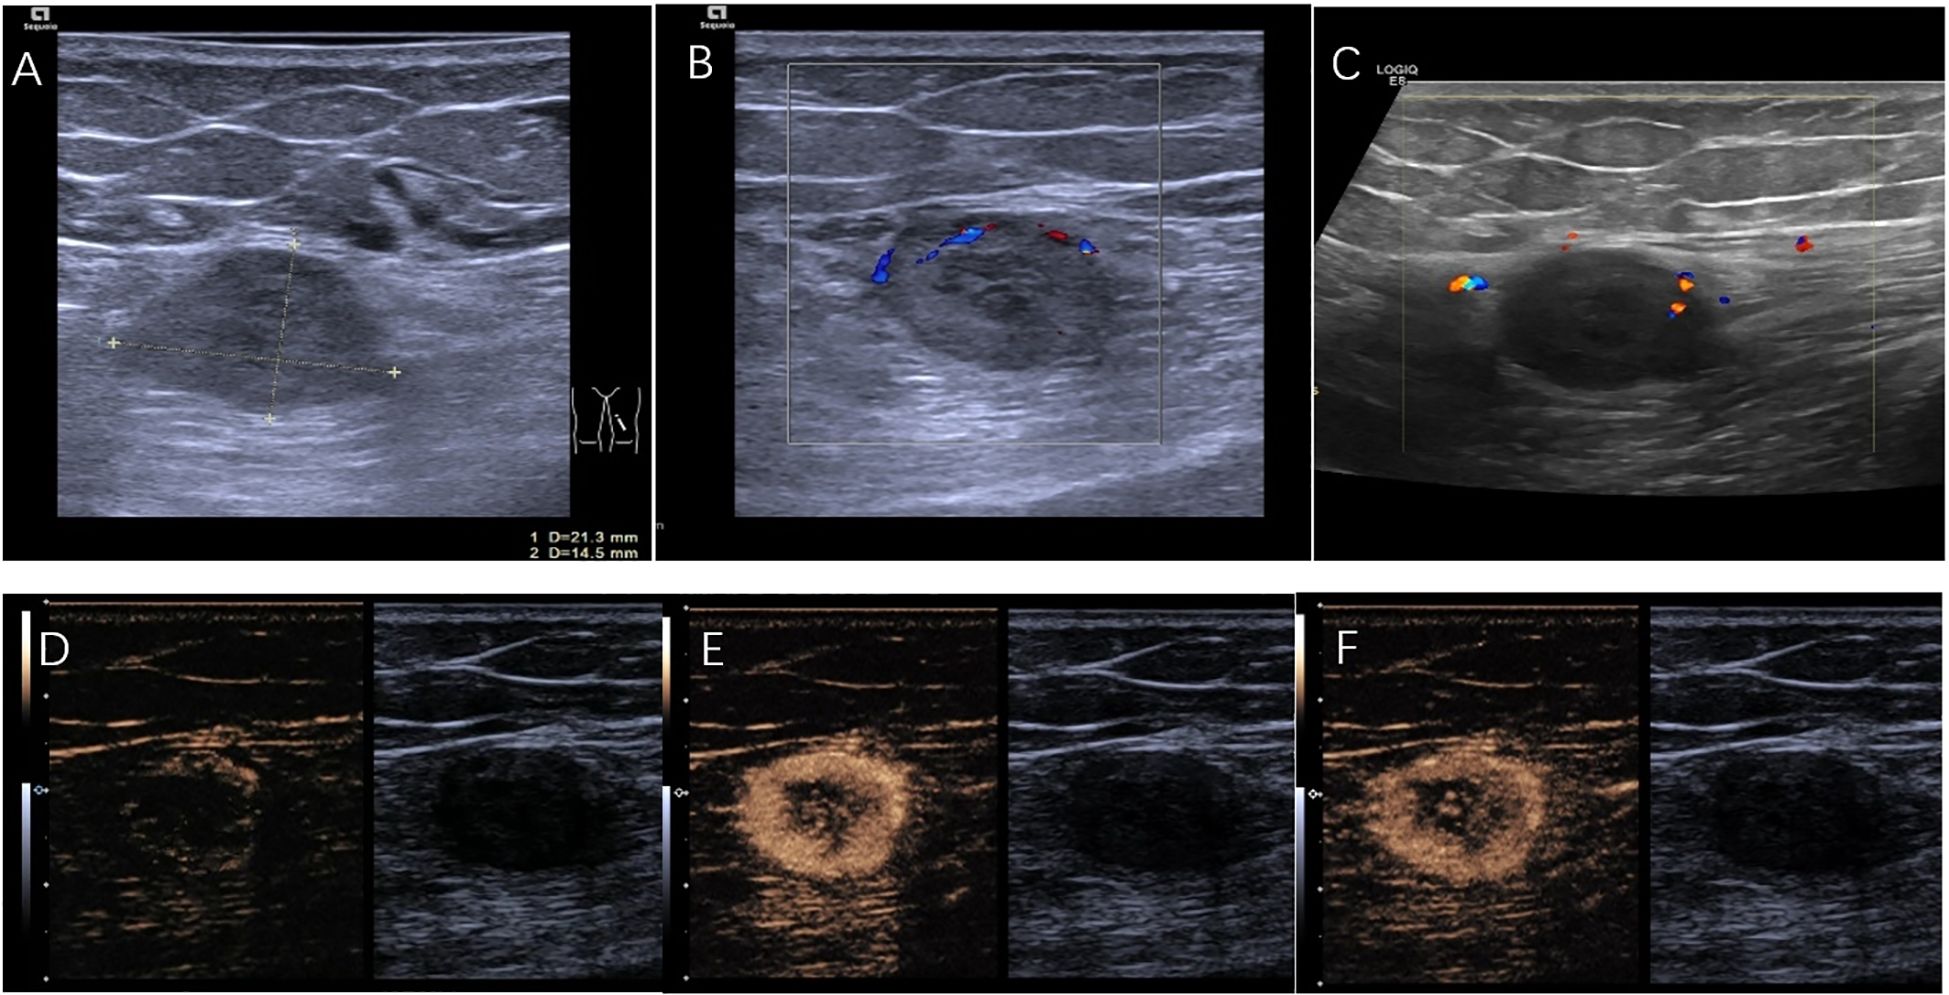

The patient was referred to the ultrasound interventional department for ultrasound-guided percutaneous biopsy to establish a diagnosis. Preoperative ultrasound was performed, two-dimensional ultrasound imaging revealed an ovoid, solid, heterogeneous, hypoechoic mass located within the muscular layer of the left upper thigh, with 21×14 mm in size (Figure 2A). The discrepancy in lesion size between MRI and ultrasound measurements can be attributed to two factors: MRI measured the maximum single-axis diameter, while ultrasound documented orthogonal dimensions; slight measurement differences among radiologists due to subjective image interpretation thresholds. Color Doppler ultrasound evaluations were performed using two different ultrasound systems: the ACUSON Sequoia (Siemens Healthineers, Germany) equipped with a linear array transducer operating at 18MHz, and the LOGIQ E8 (GE Healthcare, USA) equipped with a linear array transducer operating at 11 MHz. Doppler parameters were optimized for deep tissue assessment: the Pulse Repetition Frequency (PRF) was set to a low value to enhance sensitivity to low flow velocities, the wall filter was minimized, the color gain was adjusted to just below the noise threshold, and the color box was focused over the lesion. Both systems consistently revealed only focal and linear blood flow signals within the tumor (Figures 2B, C). In further CEUS examination, SonoVue 2.4mL was injected into the median vein of the left upper limb, CEUS findings showed rapid enhancement of the lesion starting at 17s (Figure 2D), reaching a peak at 25s with rapid heterogeneous high enhancement (Figure 2E). There was no significant increase in the size of the mass after contrast enhancement compared to its size observed on grayscale ultrasound. Clearance began at 32s and rapid faded, observed up to 5 min (Figure 2F). CEUS suggested rapid enhancement and swift washout of the left thigh lesion.

Figure 2. (A) A hypoechoic lesion of 21mm×14mm. (B) Color doppler performed with ACUSON Sequoia (linear array transducer operating at 18MHz; PRF:700 Hz; Wall Filter:60 Hz). (C) Color doppler performed with LOGIQ E8 (linear array transducer operating at 11MHz; PRF:800 Hz; Wall Filter:50 Hz). (D) CEUS demonstrates the lesion starting to enhance at the starting at 17s. (E) CEUS shows the lesion rapidly reaching its peak enhancement at 25 s. (F) CEUS illustrates the lesion fading at 32s.